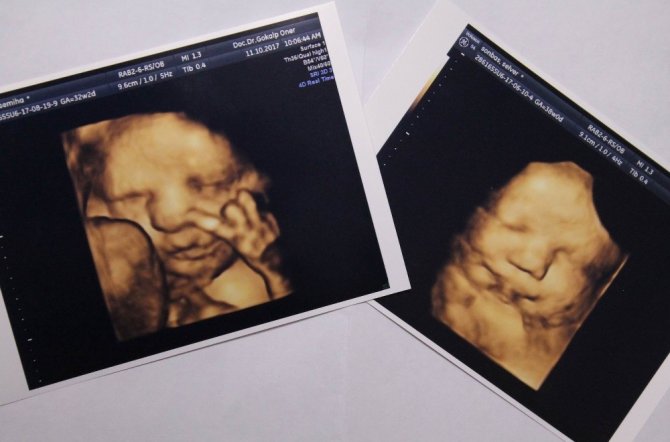

Anne karnındaki bebeklerin çekildiği dört boyutlu ultrason fotoğraflara takılan pozlar bazen şaşırtıyor. Henüz 22 haftalıkken zafer işareti yapan bebeğin fotoğrafı bunlardan en ilgi çekici olanı.

Memorial Kayseri Hastanesi Kadın Hastalıkları ve Doğum Uzmanı Doç. Dr. Gökalp Öner'in yaklaşık 2 yıldır çektiği 400'ün üzerinde, dört boyutlu ultrason fotoğraflara takılan anne karnındaki bebeklerin ilginç pozları dikkat çekiyor. Zafer işareti yapan, burnunu karıştıran, dilini çıkaran, uzun hava çeken, düşünen bebek fotoğrafları ebeveynleri hem mutlu ediyor hem de şaşkınlığa uğratıyor.

Mutlu geçirilmesi gereken hamilelik dönemini bu fotoğraflarla renklendirdiklerini dile getiren Doç. Dr. Gökalp Öner, "Bu fotoğraflarda bazen ilginç pozlar yakalıyoruz. Bebeklerimiz ağlarken, gülerken, düşünürken, zafer işareti yaparken, burnunu karıştırırken... Bunları yakaladığımızda ailenin de bizim de hoşumuza gidiyor. Böyle mutlu anları paylaşıyoruz. Çünkü gebelik süreci ve doğum, düğün gibi mutlu geçirilmesi gereken bir süreç" ifadelerini kullandı.